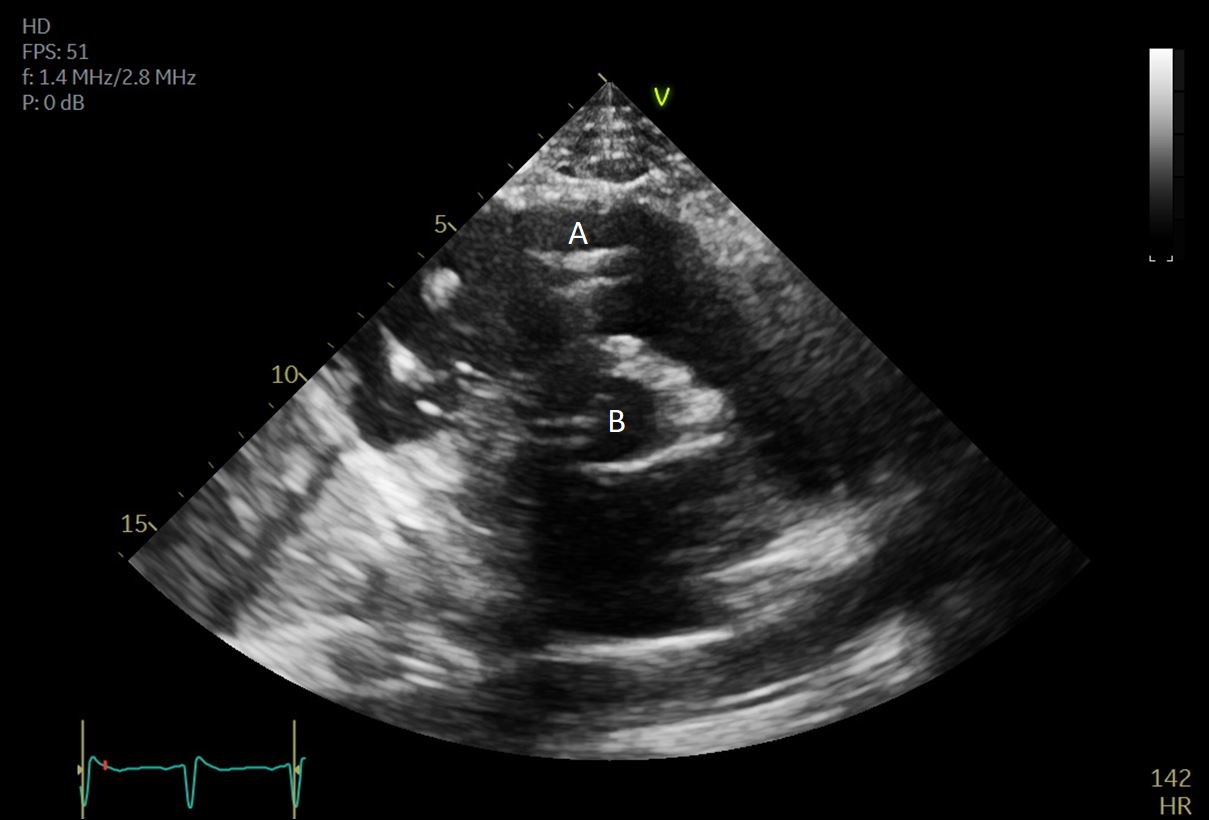

Both TTE and TEE can help with ideal positioning of the Impella (Figs. 5,6). The distance from the aortic valve to the Impella inlet should be measured. This should ideally be 3.5–4 cm for all Impella devices except for the Impella 5.5 for which it is 5 cm [15] (Fig. 7). The outlet should be 1.5–2 cm above the sinuses of Valsalva. The catheter should be angled towards the LV apex and away from the septum and mitral valve. The positioning of both the inlet in the LV cavity and the outlet above the aortic valve should be confirmed. Color flow doppler imaging can help confirm this positioning as a mosaic pattern will be visualized near the inlet and outlet ports on spectral doppler (Fig. 8). Real-time 3D echocardiography can also be used to help in visualizing Impella positioning relative to other anatomical structures (Fig. 9). After placement of the Impella, the aortic and mitral valves should be interrogated for any new or worsening regurgitation or dysfunction [16]. TEE can also help identify additional complications of Impella placement including pericardial effusion or LV free wall rupture [17].

Fig. 7.A parasternal long axis view on a transthoracic echocardiogram. The distance from the Impella inlet to the aortic valve is measured and noted to be 3.9 cm. (A) LV Cavity. (B) Impella. (C) Ascending aortic root.